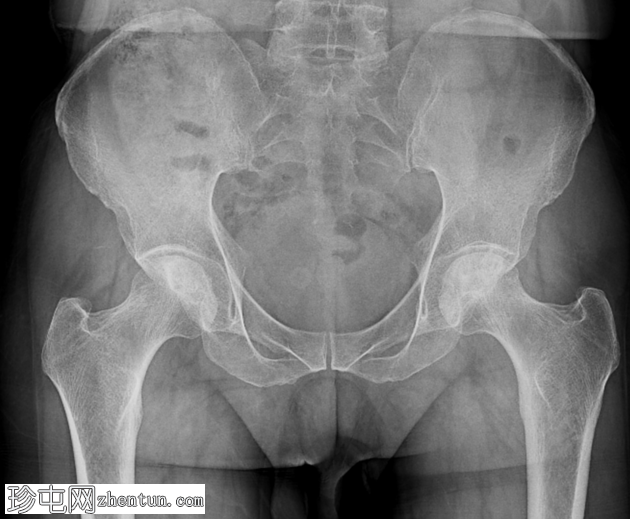

骨盆及双侧髋关节(前后位)

双侧股骨头均可见硬化区域,间杂透亮区。双侧可见可疑的软骨下透亮线(新月征)。髋关节间隙相对完整。未见明显的继发性骨关节炎改变。未见急性骨折或脱位。